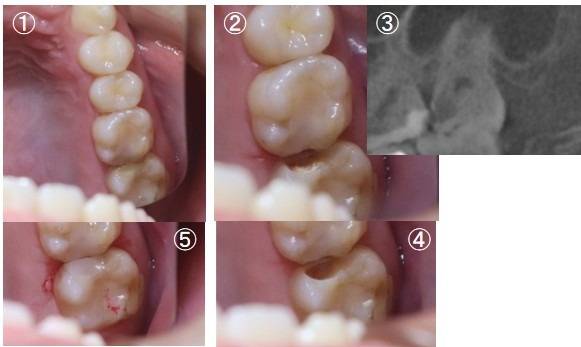

進化型インジェクタブルレジンの決定版として現在使用されているのがグレースフィルシリーズのバルクフローです。コンポジットレジン修復(CR充填)の確実なライニング材として生まれ、MI(最小限の介入)の考え方を体現する素材です。

これまで、詰め物の治療では材料と歯の間にわずかなすき間(コントラクションギャップ)ができることが問題となってきました。この新しい材料は、縮みにくいため(変化量3%以下)のため、歯と材料にすき間ができにくく、治療後の知覚過敏と二次カリエス(むし歯の再発)リスクを低減できます。

とくに、バルクフローは1度にむし歯の深い部分にまで一気に材料が固まる特徴があり、奥歯の複雑なむし歯の穴を瞬時にコーティングしてくれるのです。流れ込む際は水のように歯の細かな傷に馴染むため、患者さんの天然の歯に近い色調を自然と再現できます。

光硬化深度最大4㎜と、深いむし歯でも機能するだけでなく、重合収縮率は3%以下のためコントラクションギャップ発生を防ぎます。結果として、むし歯をとりきった深い底面から咬合面までを一括成形(バルクフィル)できるのが特徴です。

3.幅広い応用が期待